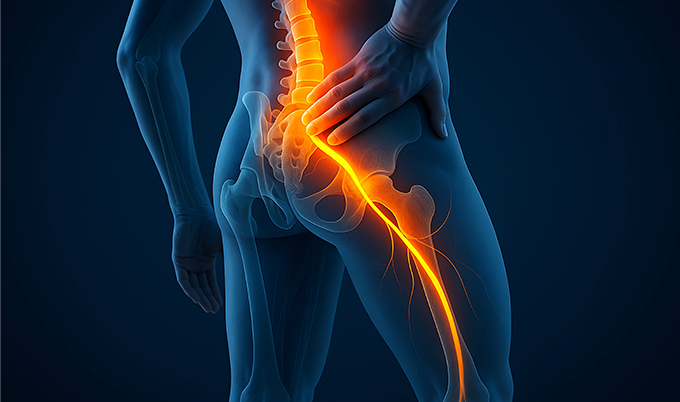

Sciatica affects 40% of adults at some point in their lives. The sharp, burning pain travels from your lower back through your buttock and down one leg.

Some patients describe electric shocks. Others report constant aching with numbness.

The sciatic nerve forms from five nerve roots that exit your lumbar spine. When disc material compresses these roots, pain radiates along the entire nerve pathway.

L4 nerve compression causes anterior thigh pain and medial leg numbness. You experience knee extension weakness making stair climbing difficult.

L5 nerve compression causes lateral leg pain traveling to the dorsum of your foot. You develop foot drop and big toe weakness visible during examination.

S1 nerve compression causes posterior leg pain radiating to your lateral foot and heel. You experience ankle weakness and difficulty standing on toes during testing.